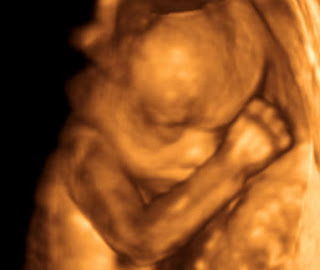

| 4D OBSTETRİK | RENAL ARTER RDUS |

| 3D OBSTETRİK | RENAL VEN RDUS |

| SUPRAPUBİK USG | 4D OBSTETRİK USG |

DÖRT BOYUTLU RENKLİ OBSTETRİK DİJİTAL CİHAZLARIMIZLA BEBEĞİNİZİN CANLI DVD ÇEKİMLERİ HASTALARIMIZA VERİLMEKTEDİR.